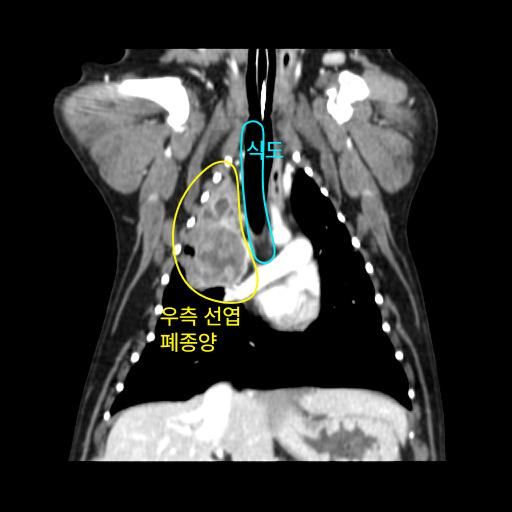

엑스레이 사진과 CT 사진(흉부 앞, 우측 옆)은 첨부하였습니다.

폐 우측 위쪽에 원발성 암이 발생한 것으로 보였습니다.

식도와 심장을 눌러서 기침을 발생시켰습니다.

나쁜 소식은 심장과 혈관이 위치한 안 좋은 부위에 암이 있다는 것이고,

좋은 소식은 심장과 혈관과 아직 붙지 않고 떨어져 있다는 것이었습니다.